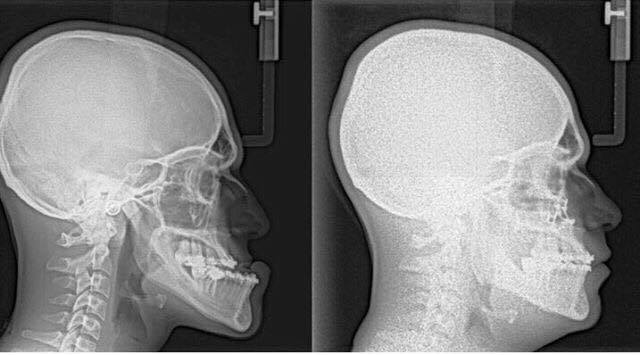

Orthognathic surgery is needed when jaws don't meet correctly and/or teeth don't seem to fit with jaws. Teeth are straightened with orthodontics and corrective jaw surgery repositions a misaligned jaw. This not only improves facial appearance, but also ensures that teeth meet correctly and function properly.

TECHNOLOGY ORTHOGNATHIC SURGERY

Dr.Al-jandan uses modern computer techniques and three-dimensional models to show you exactly how your surgery will be approached. Using comprehensive facial x-rays and computer video imaging, we can show you how your bite will be improved and even give you an idea of how you'll look after surgery. This helps you understand the surgical process and the extent of the treatment prescribed. Our goal is to help you understand the benefits of orthognathic surgery.

If you are a candidate for corrective jaw surgery, Dr.Badr will work closely with your dentist and orthodontist during your treatment. The actual surgery can move your teeth and jaws into a new position that results in a more attractive, functional, and healthy dental-facial relationship.